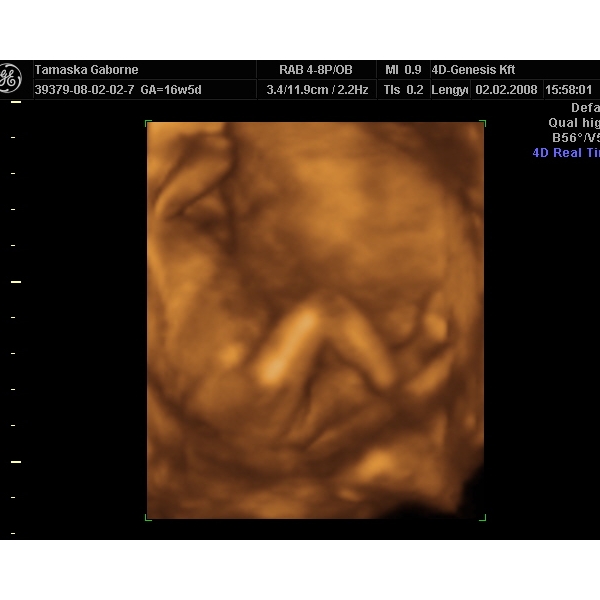

Mi még nem tudjuk, majd egy-két hét múlva belopódzom Anyuhoz egy potyaultrahangra, és megpróbáljuk kideríteni, mert a 30. heti uh-ig nem bírom ki

Jó az eü kapcsolat, mert ha akarok minden héten mehetek uh-ra.